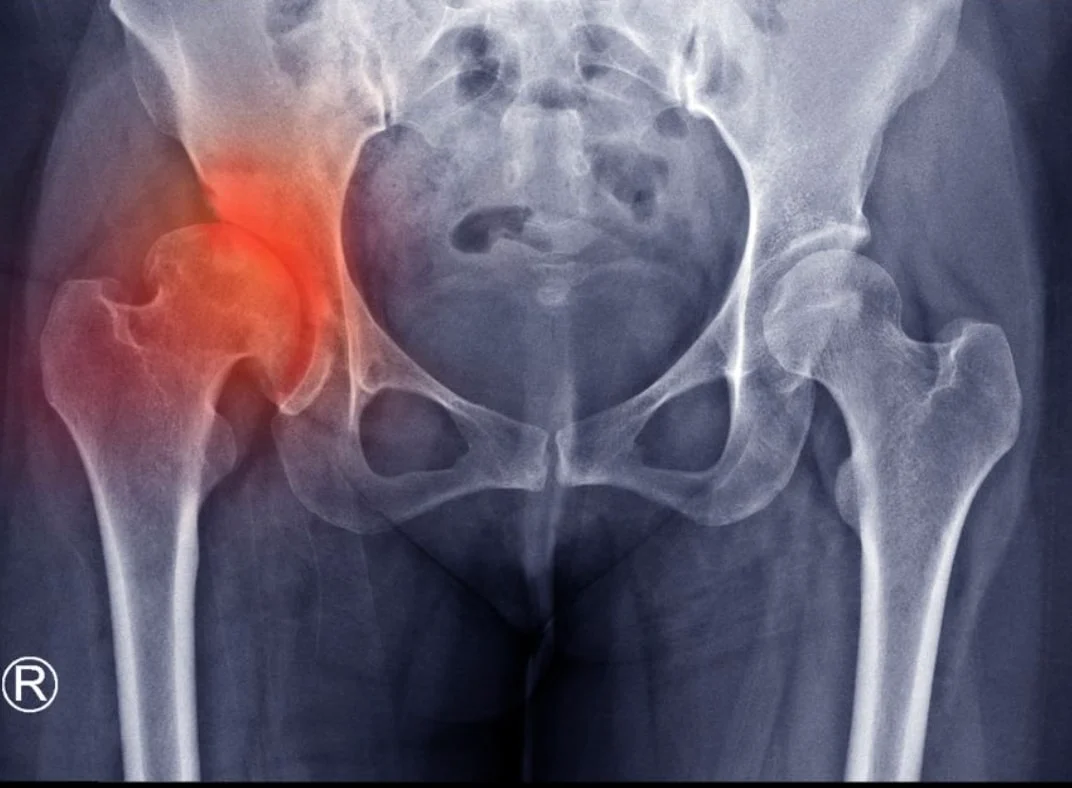

Όταν αυτός ο χόνδρος αρχίζει να λεπταίνει ή να φθείρεται, τα οστά τρίβονται μεταξύ τους, προκαλώντας πόνο, δυσκαμψία, φλεγμονή και τελικά μια κατάσταση γνωστή ως οστεοαρθρίτιδα του ισχίου (ή αλλιώς κοξάρθρωση).

Η οστεοαρθρίτιδα του ισχίου (κοξάρθρωση) είναι συχνή πάθηση που επηρεάζει πολλές ηλικιακές ομάδες, όχι μόνο τους ηλικιωμένους. Οι αιτίες που αναφέρονται (γενετική προδιάθεση, υπερβολικό βάρος, επαναλαμβανόμενες κινήσεις, τραυματισμοί) είναι σωστές και επιβεβαιωμένες από την ιατρική έρευνα.

Επίσης, τα συμπτώματα που περιγράφονται (πόνος, δυσκαμψία, αδυναμία, τριξίματα, πόνος τη νύχτα κλπ.) είναι χαρακτηριστικά της οστεοαρθρίτιδας του ισχίου και η αντιμετώπιση που προτείνεται (ήπια άσκηση, φυσικοθεραπεία, απώλεια βάρους, φαρμακευτική αγωγή, χειρουργική επέμβαση) αποτελεί τον επιστημονικά τεκμηριωμένο τρόπο διαχείρισης της πάθησης.